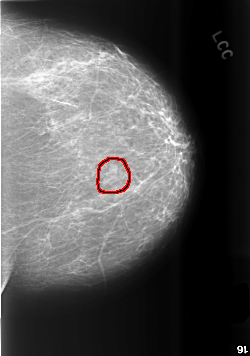

C_0496_1.LEFT_CC

LEFT_CC LINES 5688 PIXELS_PER_LINE 3992 BITS_PER_PIXEL 12 RESOLUTION 50 OVERLAY

FILE: C_0496_1.LEFT_CC.OVERLAY

TOTAL_ABNORMALITIES 1

ABNORMALITY 1

LESION_TYPE CALCIFICATION TYPE AMORPHOUS DISTRIBUTION CLUSTERED

ASSESSMENT 4

SUBTLETY 4

PATHOLOGY MALIGNANT

TOTAL_OUTLINES 1

BOUNDARY